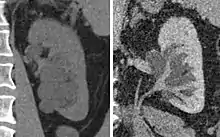

Renal ultrasonography of hydronephrosis caused by a left ureteral stone.

Hydronephrosis due to a kidney stone at the ureteral vesicular junction seen on CT scan